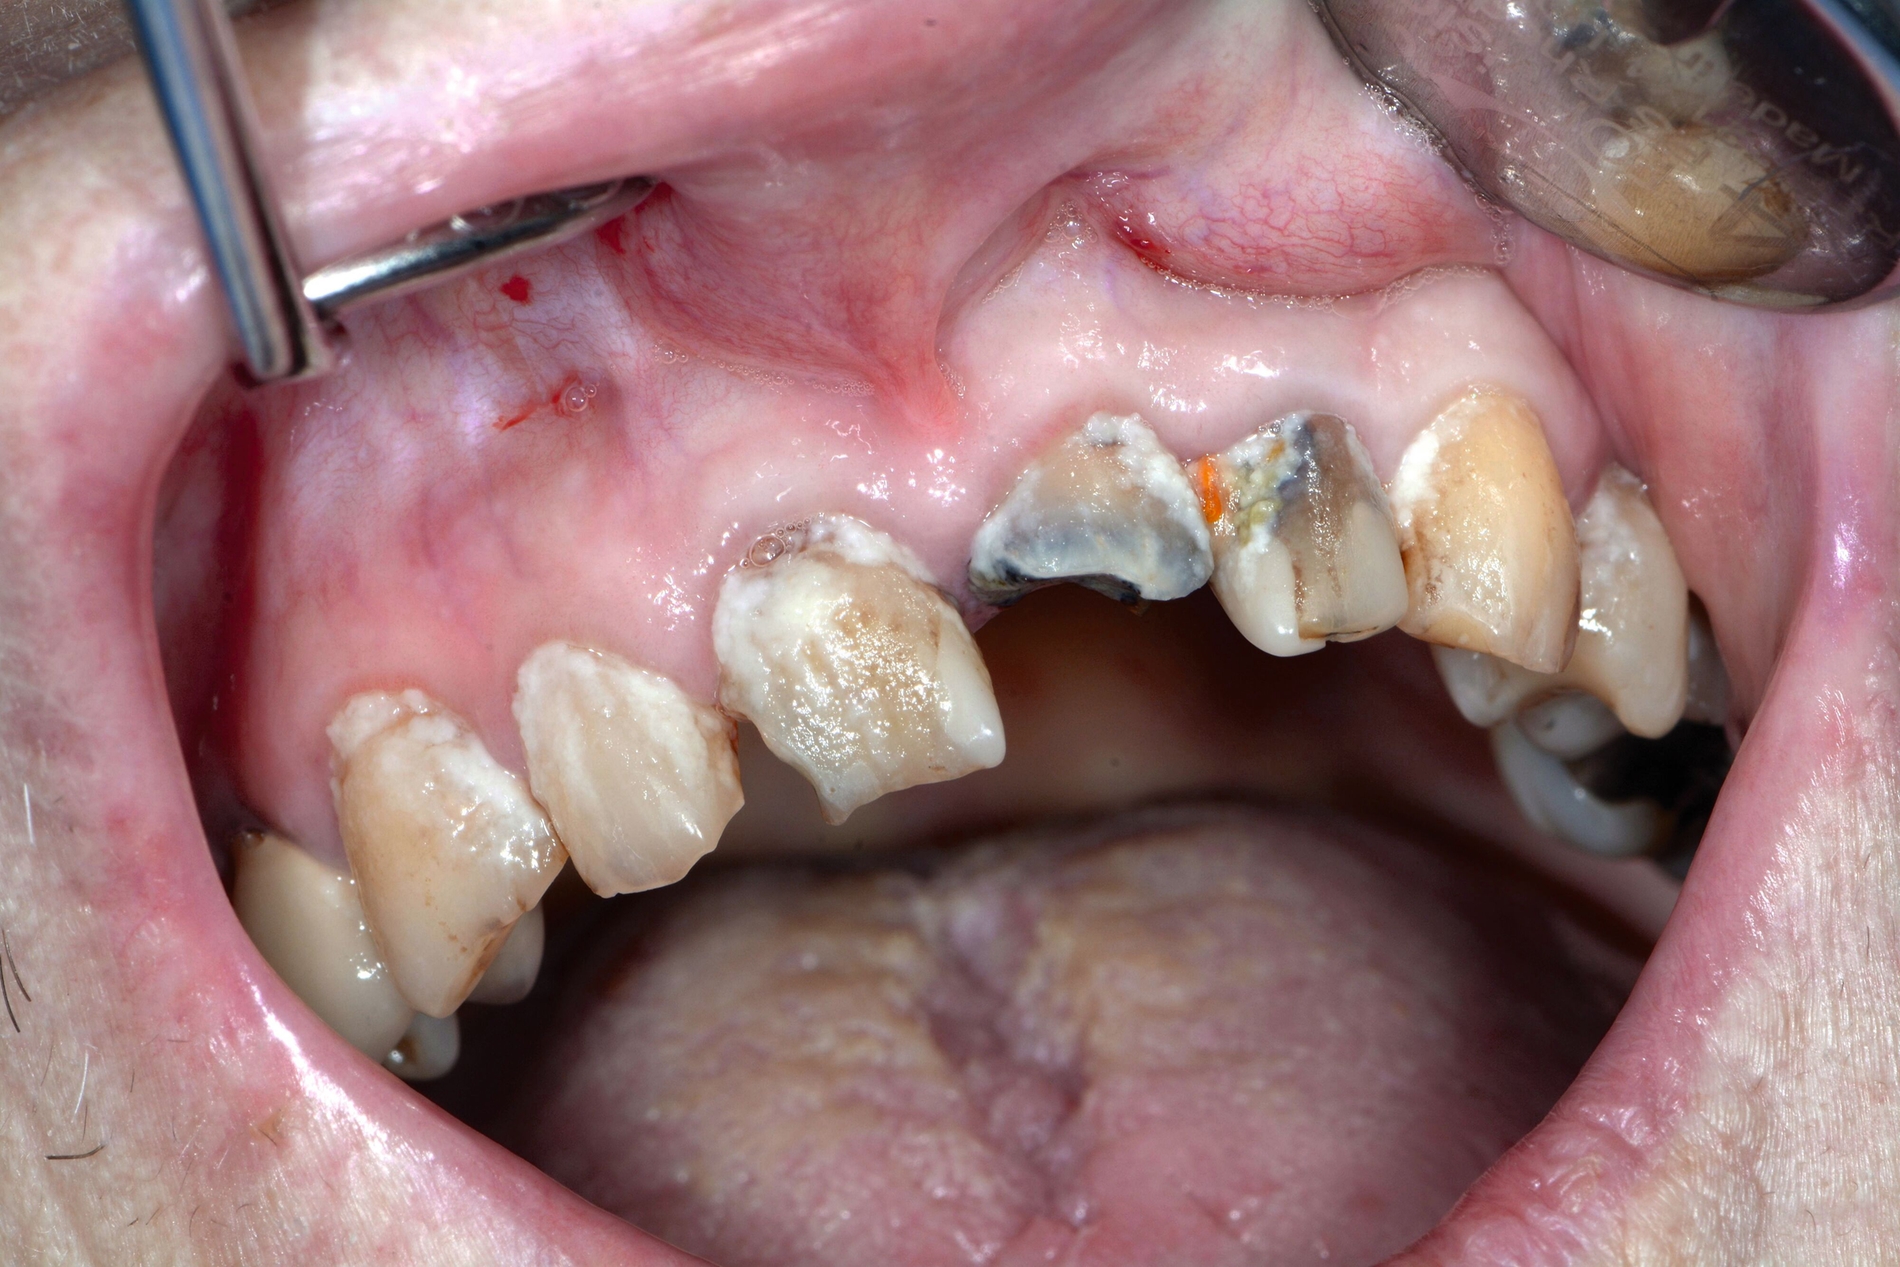

Auch wenn sich Karies, Parodontitis und dentale Traumata bei dieser vulnerablen Hochrisikogruppe in absehbarer Zeit wohl nicht gänzlich vermeiden lassen, ermöglicht die regelmäßige zahnmedizinische Kontrolluntersuchung, dass einzelne Befunde frühzeitig identifiziert und mit moderatem Aufwand therapiert werden können (Abbildung 5). Bei stark reduzierter Therapiefähigkeit sollten als Minimalziel die oralen Strukturen schmerz- und entzündungsfrei sein, um lebensbedrohliche Komplikationen wie Pneumonien oder Bakteriämien zu verhindern. Parodontale und periimplantäre Erkrankungen sollten im Kontext des allgemeinen Gesundheitszustands, der physiologischen Alterung des Immunsystems und der allgemeinen Körperfunktion beurteilt werden [Paris et al., 2020; Müller et al., 2022]. Prothetische Rehabilitationen sind zum Erhalt der Kaufunktion und der mundgesundheitsbezogenen Lebensqualität je nach Lokalisation und Ausmaß des Zahnverlusts sinnvoll, bedingen aber ein Mindestmaß an Mitarbeit von Patient und betreuendem Umfeld. Eine möglicherweise reduzierte Adaptationsfähigkeit an neu angefertigten Zahnersatz gilt es besonders bei neurodegenerativen Erkrankungen im Vorfeld der Therapie zu besprechen [Nitschke et al., 2021].

Patientinnen und Patienten mit stark reduzierter Therapiefähigkeit profitieren in besonderem Maß von zeiteffektiven Methoden und Materialien, zum Beispiel Bulk-fill-Kompositen, Reparaturfüllungen, Glasionomerzementen oder Intraoralscans. Die Therapiefähigkeit kann – ähnlich wie in der Kinderzahnmedizin – durch ein vertrauensvolles Verhältnis optimiert werden. Anders als in der Kinderzahnmedizin gibt es in der Alterszahnmedizin aber keine altersassoziierten Kontraindikationen für zahnmedizinische Interventionen. Voraussagbare Therapieergebnisse sind von besonderer Bedeutung, um erneute Behandlungen zu vermeiden. Das gesamte Spektrum zahnmedizinischer Interventionen kann bei der Behandlung von Personen mit Pflegebedarf sinnvoll sein. Die Abbildungen 6 bis 9 zeigen zahnmedizinische Interventionen bei Personen mit ausgeprägter Frailty (Stufe 7 der klinischen Frailty-Skala).